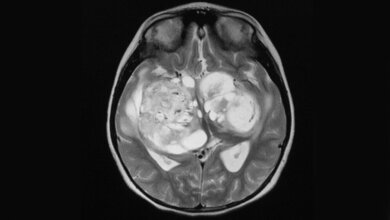

Schnelles Wachstum, starke Infiltration des umliegenden Gewebes und häufige Rückkehr auch nach erfolgreicher Therapie innerhalb weniger Monate: Das sind die Kennzeichen des sogenannten Glioblastoms. Der Tumor entwickelt sich aus dem Stützgewebe des Gehirns, den Gliazellen; er zählt zu den häufigsten Hirntumoren bei Erwachsenen. Das Glioblastoma multiforme ist die aggressivste Variante dieser Krebsart.

Erste Symptome sind die klassischen Anzeichen eines erhöhten Hirndrucks wie etwa Kopfschmerzen, Schwindel und Erbrechen. Später leiden die Erkrankten häufig unter neurologischen Ausfällen, zu denen Seh- und Sprachstörungen sowie Lähmungserscheinungen gehören, aber auch epileptische Anfälle und psychische Veränderungen.

Die Standardbehandlung besteht aktuell aus den drei Bausteinen Operation, Bestrahlung und Chemotherapie. Der Erfolg dieser Maßnahmen ist begrenzt: Ein Jahr nach der Diagnose sind maximal 50 Prozent der Betroffenen, nach zwei Jahren nur noch zehn bis 15 Prozent am Leben; die mittlere Überlebenszeit liegt bei etwa 15 Monaten.

Aus diesem Grund unterstützt die Deutsche Krebshilfe e.V. jetzt mit rund 170.000 Euro ein neues Forschungsprojekt, das eine neuartige Therapie entwickeln will. Daran beteiligt sind Wissenschaftler und Ärzte an der Klinik für Strahlentherapie und der Neurochirurgischen Klinik des Uniklinikums Würzburg sowie am Lehrstuhl für Biotechnologie und Biophysik der Universität Würzburg. Ihr Ansatz: Mithilfe des sogenannten „molekularen Targetings“ wollen die Forscher die Glioblastomzellen daran hindern, sich im Hirngewebe auszubreiten.